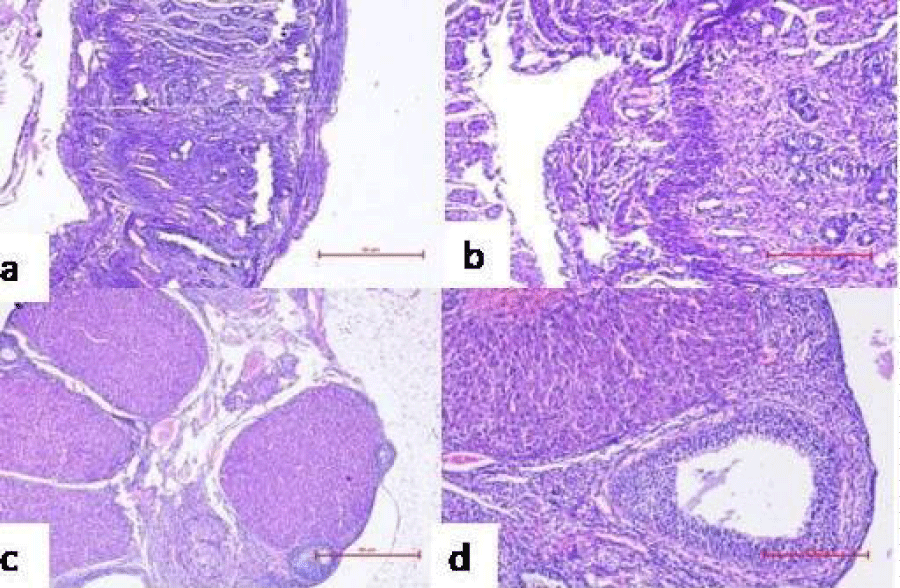

Figure 10: Representative microphotographs of histological examination of reproductive organs of mice administered with PBS/individual bacterial strains for 10 consecutive days showing pregnancy related changes viz. proliferation of endometrium with decidualization of stroma in the uterus at 40X (a) and 100X (b), ovary showing the presence of corpus luteum at 40X (c) and 100X (d).

Histological investigation of reproductive organs to assess pregnancy related changes

Further, ovary and uterus were observed histologically on GD14 to determine pregnancy related changes in reproductive organs of group I-V. Presence of corpus luteum (an indicative of the pregnancy) induced luteal phase, which persists due to the secretion of progesterone that plays a momentous role in maintaining and establishing pregnancy, was observed in the ovary of mice administered with PBS (Figure 10c). The uterus was also found to have extensive proliferation of uterine glands, increased thickness of endometrium and formation of decidua’s, signifying conception (Figure 10a). However, the uterus of group VI, VII, VIII, did not showed any gross morphologic differences on day 14 post mating (Figure 12a). The primary follicles of the group showed normal appearance and the presence of atretic follicles indicated absence of formation of corpus luteum in ovary (Figure 12c).

Histological examination of the ovary and uterus was conducted to ascertain any pregnancy related changes. These studies were done by taking sections from reproductive tracts of control mice administered with PBS and mice inoculated with 101 cfu/20 µl of individual bacterial strains and consortia of bacterial strains. Histological examination of control mice administered with PBS and mice inoculated with individual strains showed pregnancy related changes such as presence of corpus luteum in ovary and decidua formation in uterus while no such histological changes in the reproductive organs viz. ovaries and uteri of mice inoculated with consortia of bacterial strains were observed.